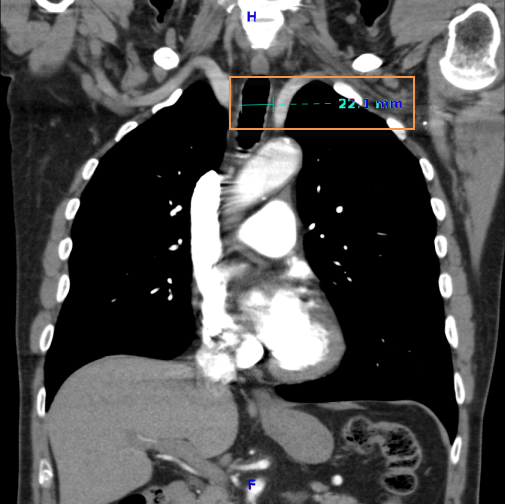

Távolság méréséhez: